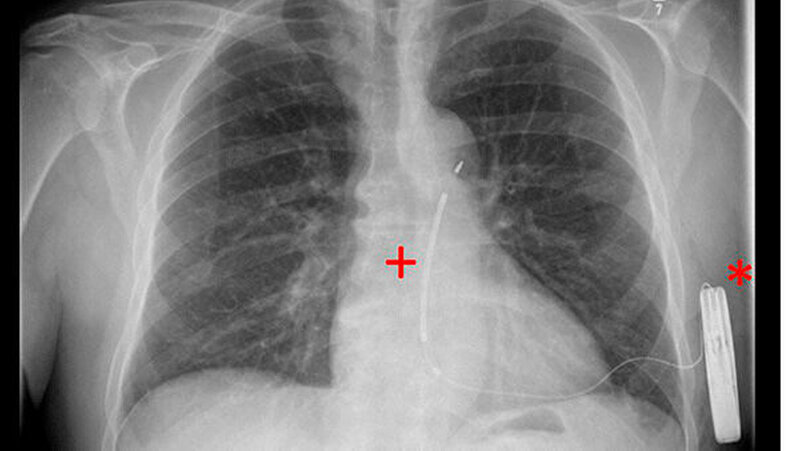

Seit 2009 steht mit den sogenannten subkutanen Defibrillatoren ein neuer technologischer Ansatz zur Verfügung: Die Aggregate werden auf der linken Seite des Brustkorbes implantiert, die Elektrode verläuft dabei nur noch unter der Haut vor dem Herzen. Seit Februar 2015 ist die zweite Generation dieser Defi-Variante verfügbar und jetzt weltweit erstmals im Herzzentrum Leipzig eingesetzt worden. Das Gerät ist rund 20 Prozent flacher und weist im Vergleich zu seinem Vorgänger eine um 40 Prozent längere Batterielaufzeit auf.